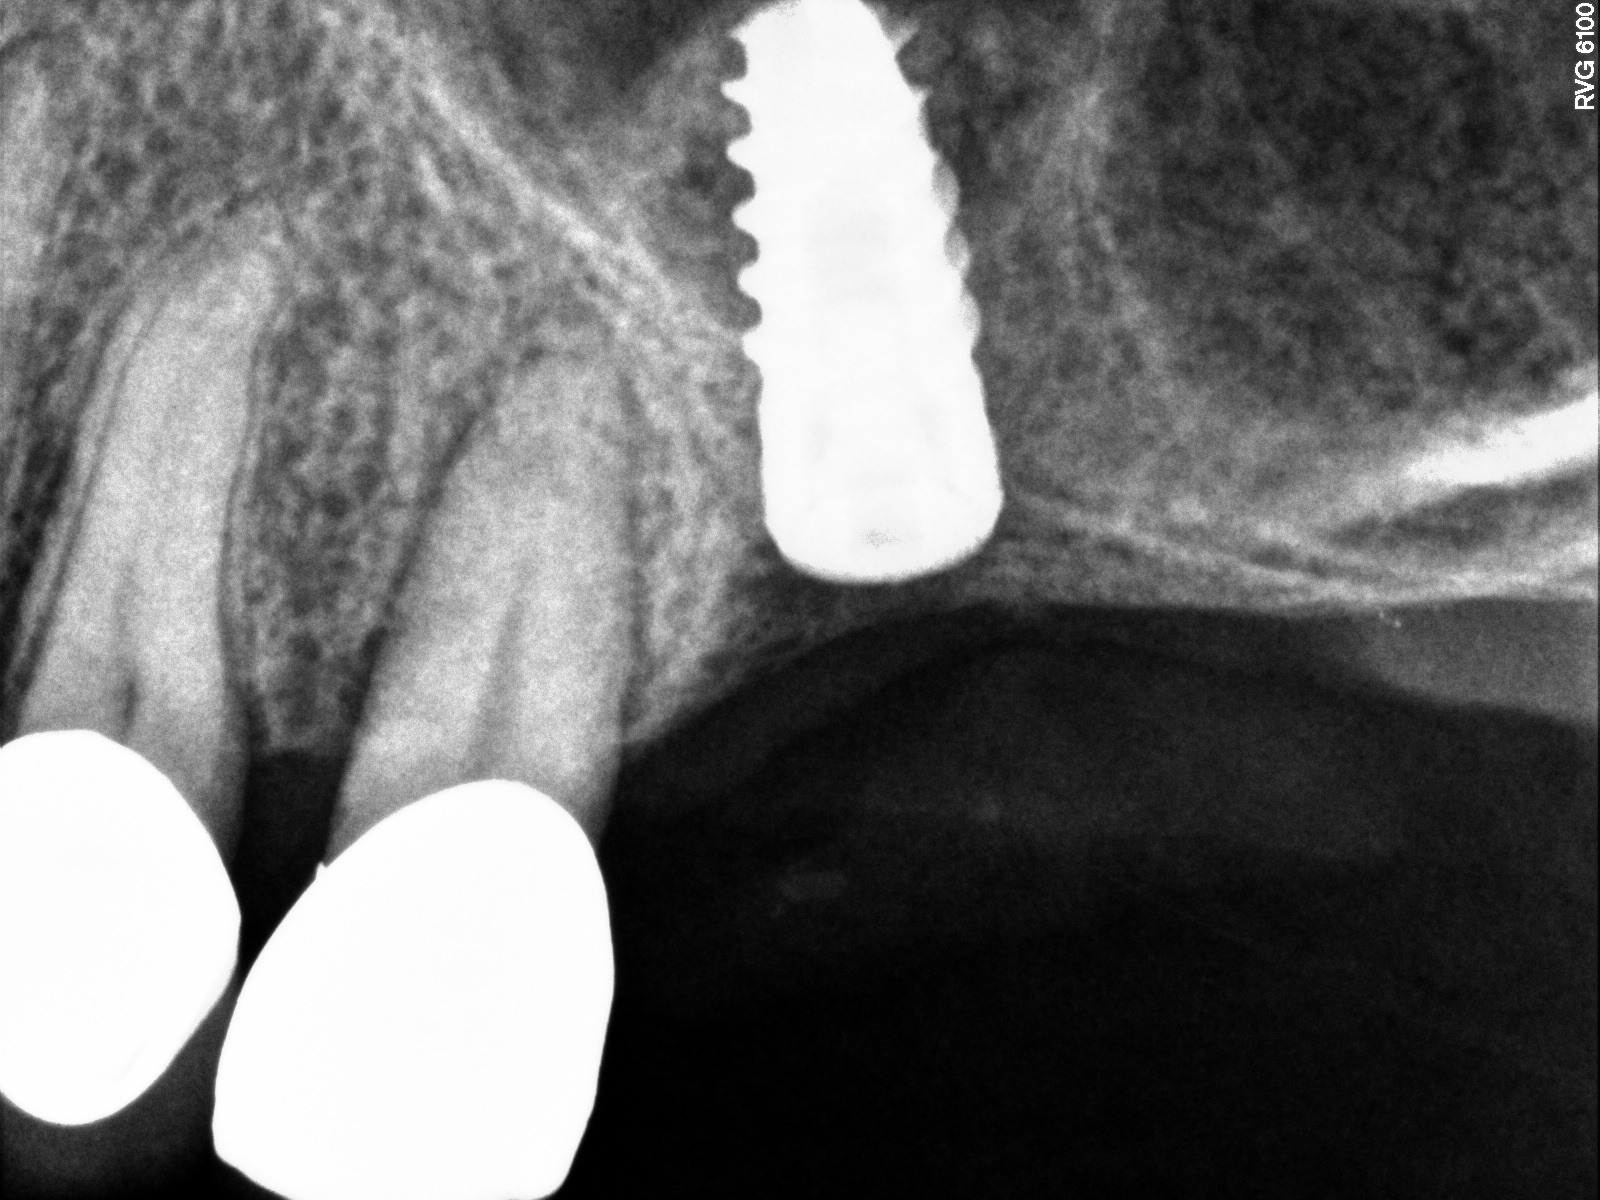

Radiograph of implant No. 14 with sinus augmentation, day of placement. The floor

of the sinus has been raised about 7 mm to 8 mm.

Fig. 15